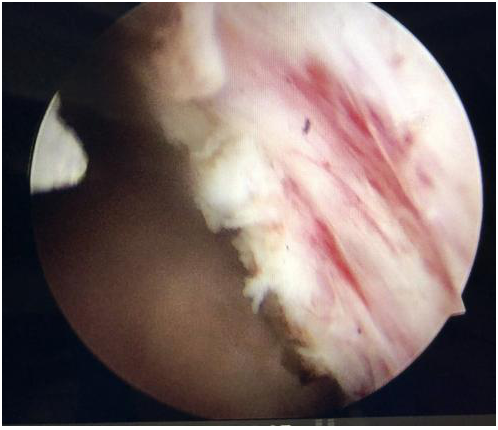

沿前列腺包膜剜除

粉碎剜除前列腺組織